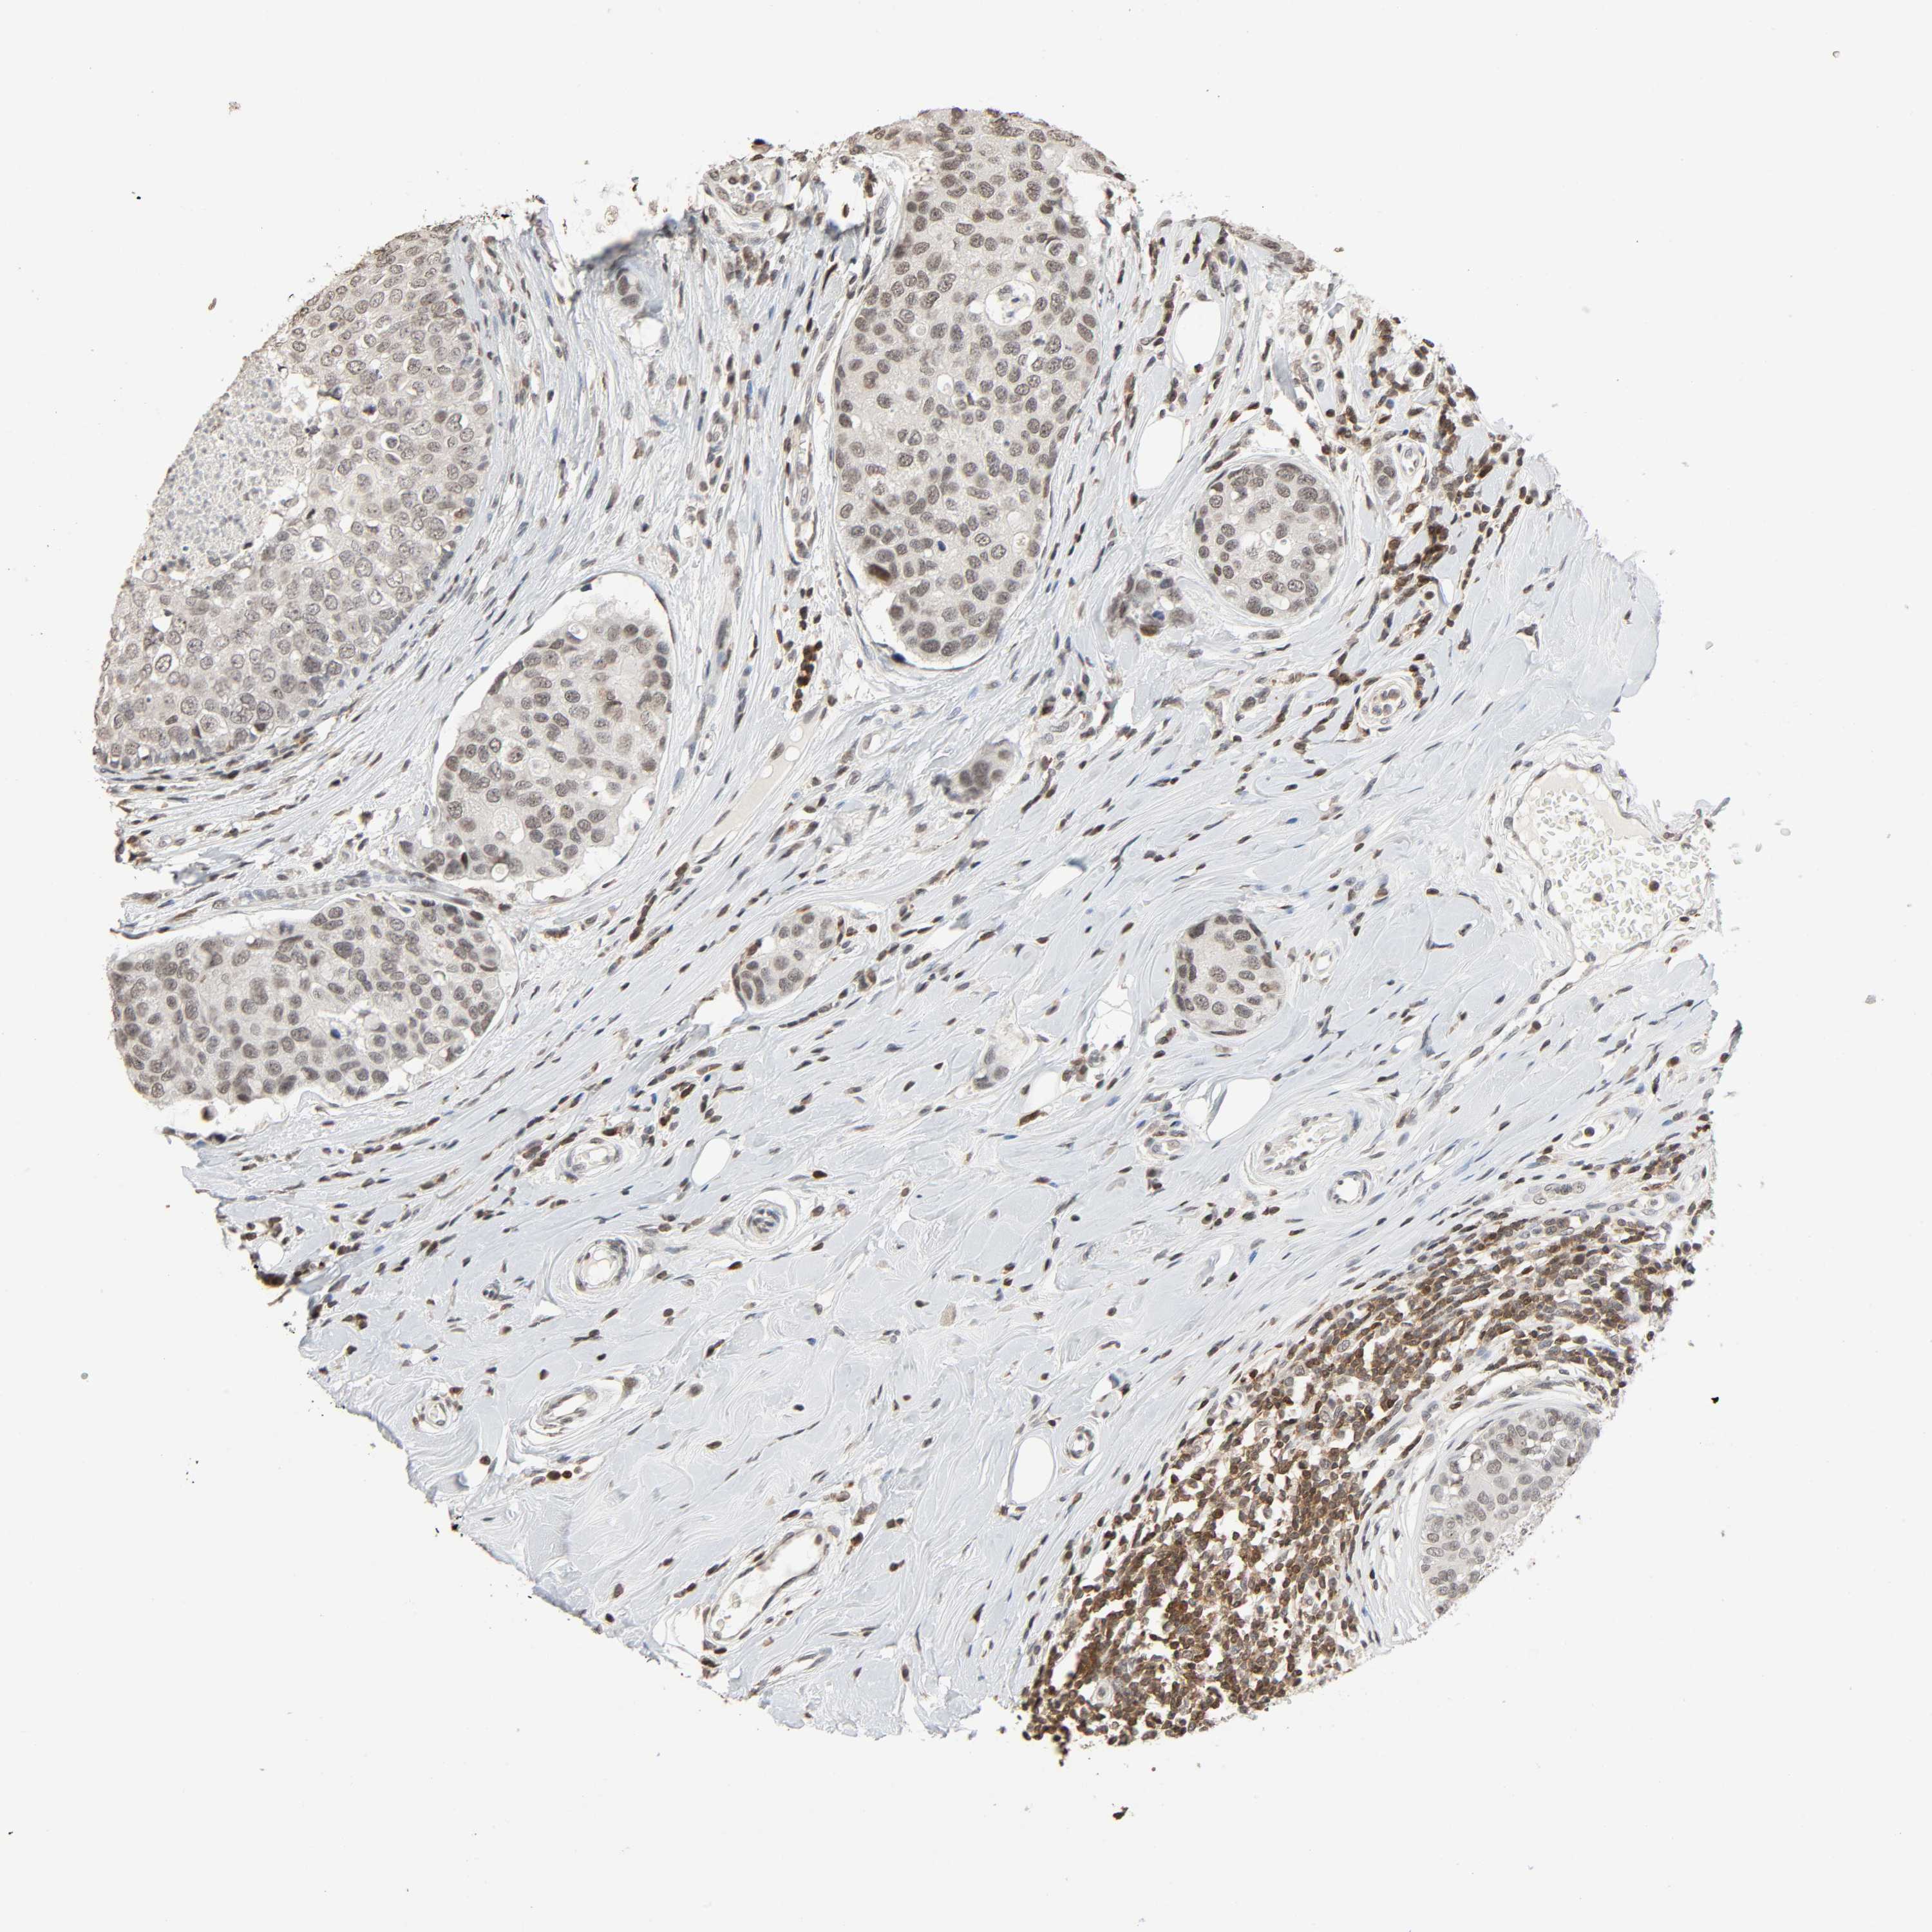

CANCER BREAST CANCER Show tissue menu

Breast cancer

Human cancer